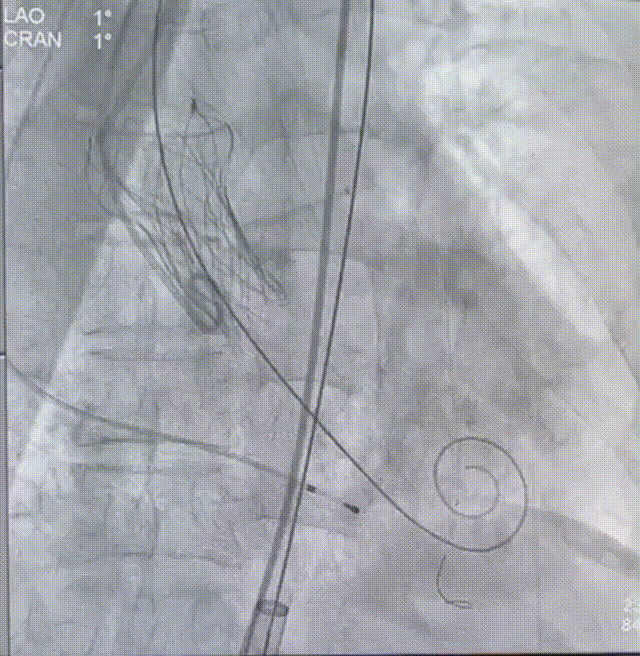

术中操作

22mm球囊预扩

瓣膜定位

瓣膜释放至75%

瓣膜脱钩

瓣膜完全释放

22mm球囊后扩

完成植入

术后即刻超声显示:释放后瓣膜工作正常,患者的跨瓣压差由术前的83mm/Hg改善至术后的4mm/Hg,患者获益明显。